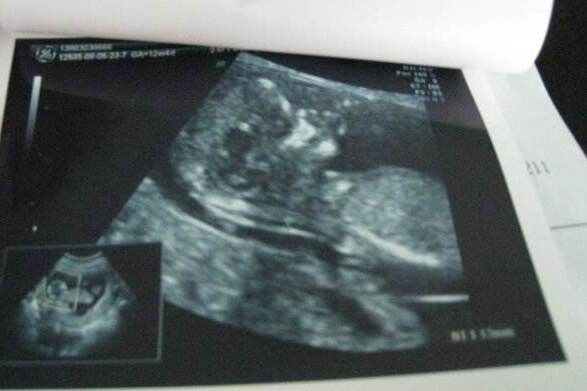

NT检查与孕周关系密切

NT即是检查胎儿颈项透明层,指胎儿颈后皮下组织液内液体积聚的厚度,反映在超声声像图上,即为胎儿颈椎水平矢状切面上测量颈后皮肤至皮下软组织之间无回声层的最大厚度。 NT的变化与孕周密切相关,规定测量其…